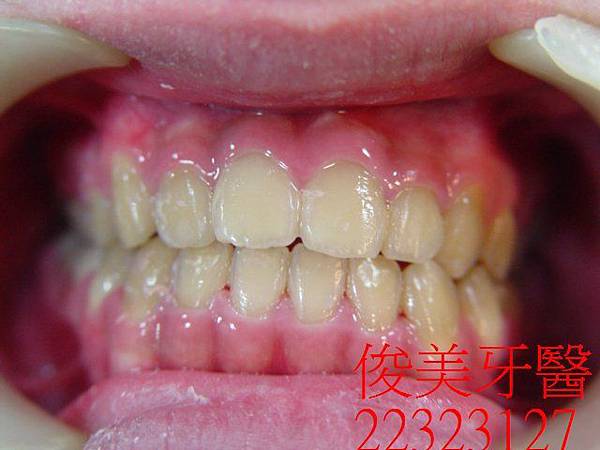

矯正器拆除了,患者非常開心,家長也很滿意,目前配戴維持器,定期檢查即可。

矯正結束後的狀況非常良好。

追蹤好幾年,目前下顎及上顎智齒皆已在適當時間拔除.....